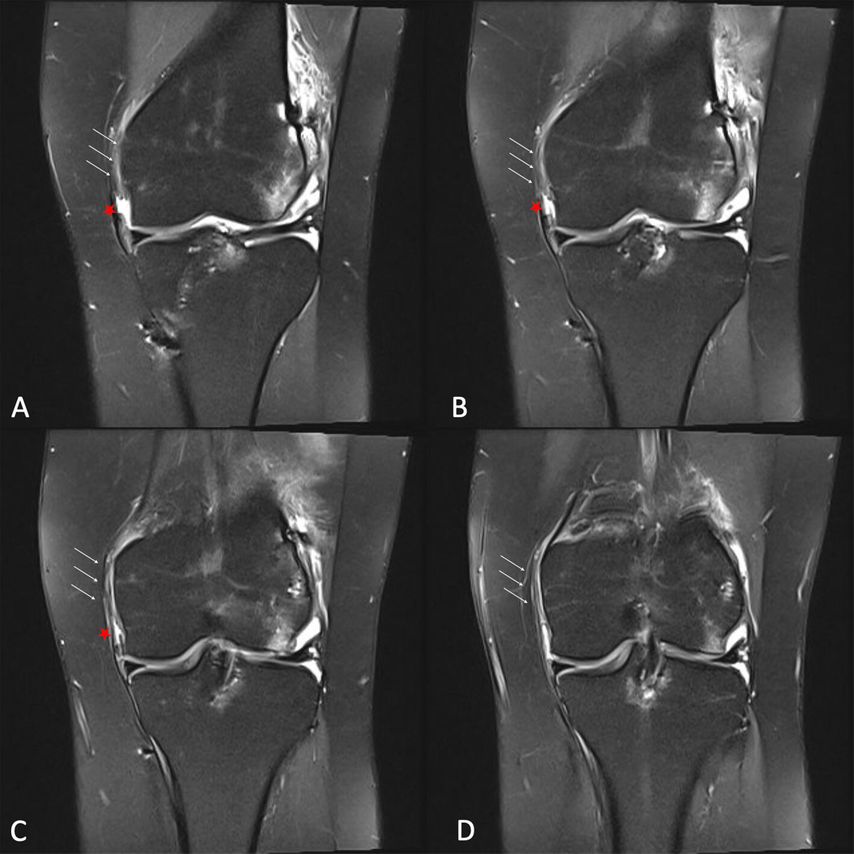

Abb. 3: MRT-Untersuchung einer chronischen medialen Instabilität. A–D: 4 aufeinanderfolgende Schichten einer koronaren STIR-Sequenz zeigen das ausgedünnte bzw. vernarbte sMCL am femoralen Ansatz (Pfeile) und den Defekt im meniskofemoralen Anteil des dMCL (roter Stern)

In der Analyse des Versagens von VKB-Rekonstruktionen wurden in den letzten Jahren persistierende mediale Instabilitäten (vor allem auch Insuffizienz des AML/dMCL, verbunden mit erhöhter Außenrotation) als wesentlicher Risikofaktor identifiziert (Abb. 3, Abb. 9A).